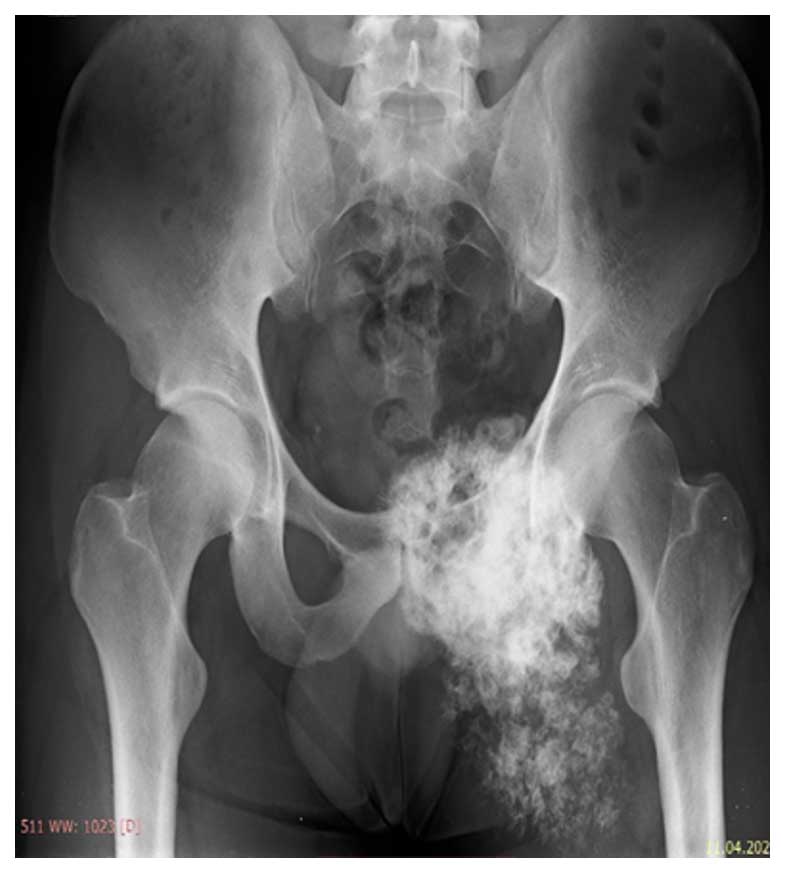

Ameliyat Esnası: SİAS fiksasyonu ve prolen mesh ile yumuşak doku rekonstrüksiyonu görülmekte.

Ameliyat Esnası: Rezeksiyon sonrası kemik greftinin fiksasyonu görülmekte.